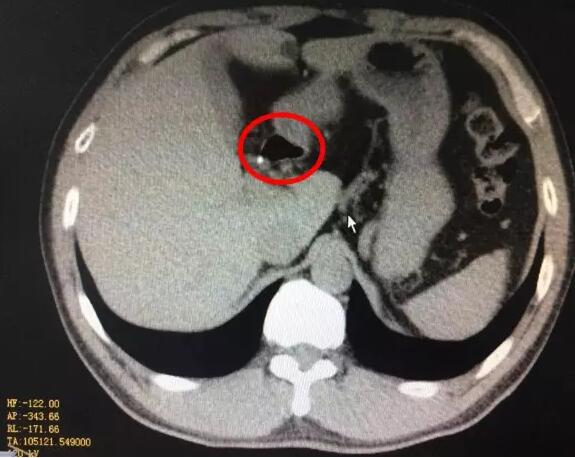

很快,化验结果出来了,血淀粉酶2714U/L,腹部CT提示胰腺水肿,急性胰腺炎诊断明确。立即给予胃肠减压、制酸、抑酶等综合治疗。第三天复查CT提示坏死性胰腺炎,只有少量胰腺组织残留,并出现肺功能、肝功能受损和腹腔积液等并发症。

据当时参与抢救的结石科主任介绍,我们这位同事发生急性胰腺炎的罪魁祸首就是那颗小结石,是典型的胆源性胰腺炎。由于结石从胆囊掉出,嵌顿在壶腹部,使胆道内压力剧烈增高,高压的胆汁逆流胰管,造成胰腺腺泡破裂,胰酶进入胰腺间质而发生胰腺炎。如果处理不及时,可发展为重症胰腺炎,死亡率很高。万幸的是该同事的结石自己掉出来了。